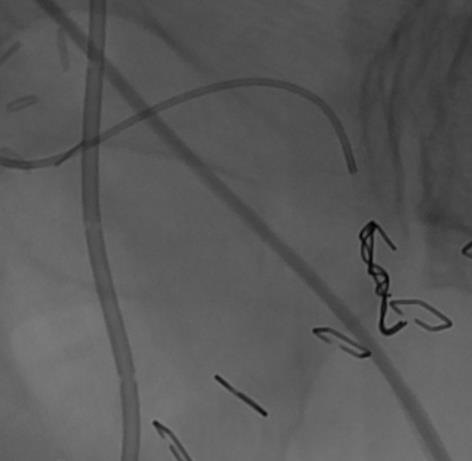

外伤后出血的栓塞

外伤后可见造影剂外溢 |

微导管选择至出血血管 |

出血血管的微弹簧栓子栓塞 |

栓塞后造影 |